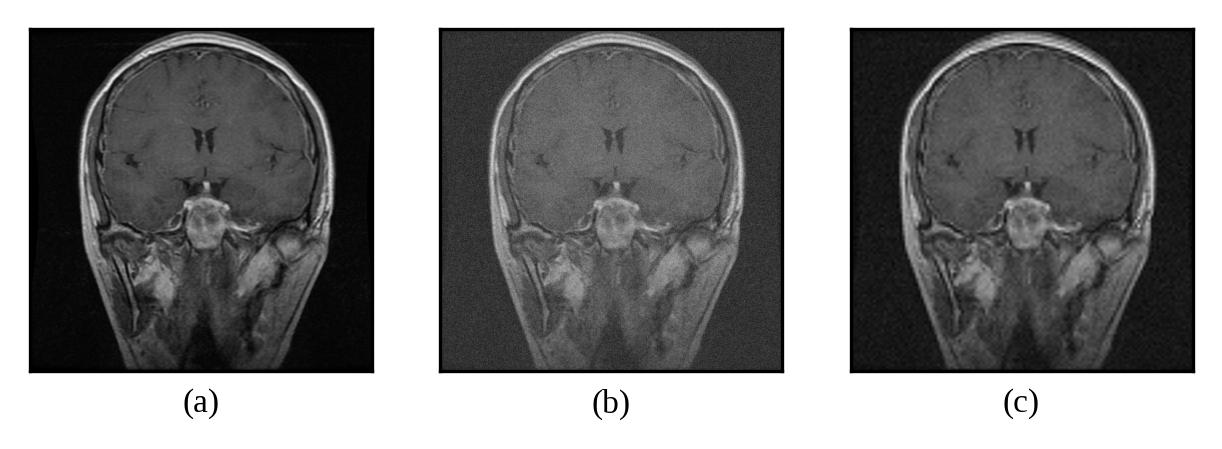

Representative denoising results are illustrated in Figures 2 through 7, demonstrating the visual improvement achieved by both thresholding methods across different noise levels.

Refer to caption

Figure 3: (a) Original Image, (b) Noisy Image(μ=0\mu=0, σ=10\sigma=10), (c) Denoised Image (with threshold value τuniversal\tau_{universal})